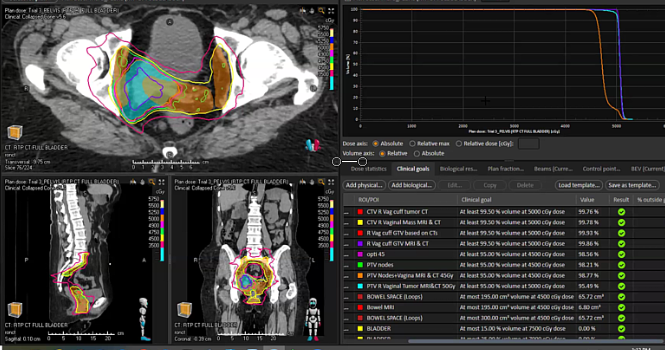

endometrial adenocarcinoma, para-aortic nodes, PET CT, diabetes, charcot arthropathy, groin nodes, pelvis, negative cervical margins, cisplatin, small bowel, Harkenrider, contouring, MRI, tumor, vaginal bleeding, relapse, persistence, cylinder, dose distribution, dosimetry, brachytherapy, fractio...

squamous cell carcinoma, dysplasia, PET, SIB, brachytherapy, endocervical, MRI, nodal location, inguinofemoral, right external iliac, CTV, deescalation, dosimetry, sigmoid, hysterectomy, concurrent chemoradiation, stenotic cervix, abdominal infection, external planning, avoid structure, antibioti...

chemotherapy, radiation therapy, sandwich regimen, brachytherapy, well differentiated endometrioid adenocarcinoma, neoadjuvant chemotherapy, small bowel, dilation, dosimetry, gross disease dose, MRI, cirrhosis, external beam radiation, Rotte Y applicator, CT scan, dual tandem, 3-D printing, endom...